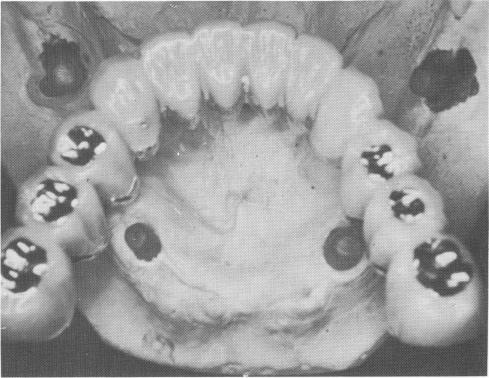

Fig. 11-144. An acrylic-over-gold full arch fixed denture with six gold occlusal stops is seen on the stone model.

3 Acrylic over gold full arch fixed denture with six gold occlusal stops